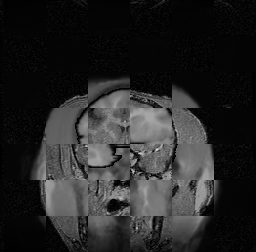

For each of the 10 subjects, we show checkerboard slices in each direction (1) before registration, first row; (2) after rigid->scaleversor->affine registration, second row; and (3) after BSpline registration, third row.

Issac

Issac is a good example of BSpline registration failure.

Ron noted, the reason might be that Issac had his mouth open, unlike most of the subjects registered successfully.